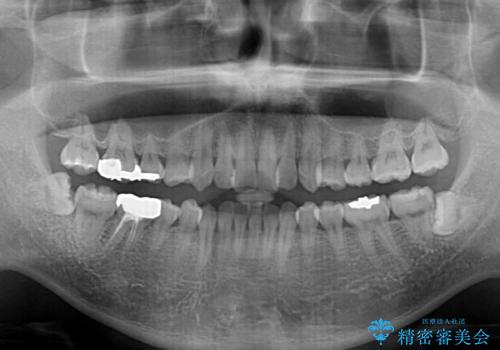

- 上下前歯のデコボコと突出感を気にして来院された患者様です。

矯正治療後に銀歯をセラミックに替えたいとの要望があり、概ね歯列が整ったところで銀歯をセラミックに替え、仕上げにインビザライン1セットを使用して最終的に歯列を整えました。